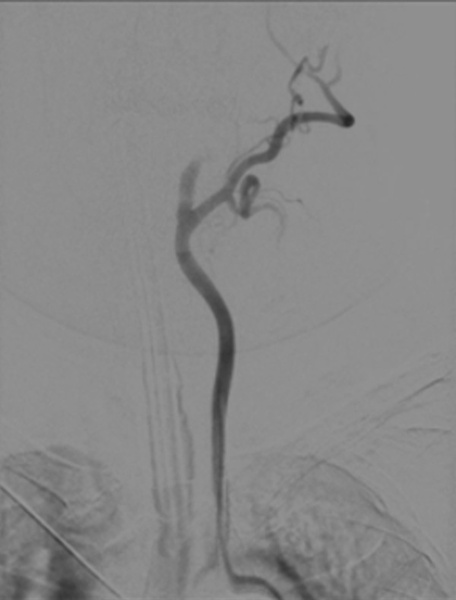

Description of the treatment Ultrasound-guided right femoral puncture was performed using a micropuncture kit. An 8F sheathless long femoral introducer was advanced over a 0.035″ guidewire into the descending aorta.​

After removal of the introducer dilator, the 0.088″ large-bore aspiration catheter (SOFIATM Flow 88), the diagnostic catheter, and the guidewire were advanced together and navigated up to the proximal internal carotid artery.​

At this level, the diagnostic catheter was withdrawn, aspiration was initiated using a pump, and the SOFIATM Flow 88 was advanced into the intracranial internal carotid artery.​

The aspiration catheter was then withdrawn under continuous aspiration, with simultaneous manual aspiration through the introducer using a 60-mL VacLok syringe, resulting in clot removal and vessel recanalization.​